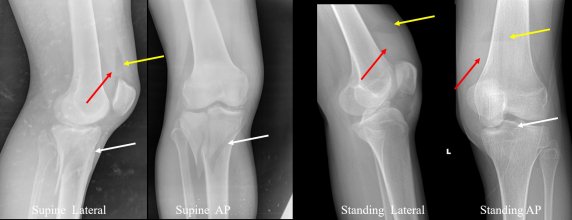

Definition Lipohemarthrosis refers to the presence of fat and blood within the joint space, resulting in a fat–fluid level due to density dif ...